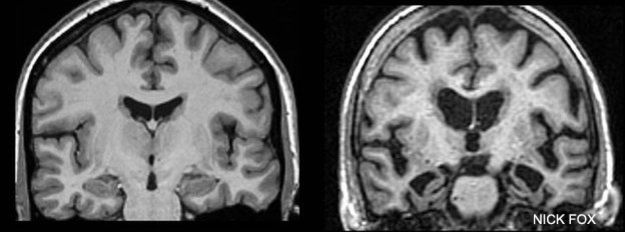

"Estas familias nos ofrecen información muy valiosa sobre los primeros cambios que suceden en el cerebro, incluso antes de que aparezcan los síntomas", explica Nick Fox, investigador de UCL.

A la izquierda, el escáner de una persona sana, a la derecha, el de una persona con Alzheimer. Imagen cortesía de Nick Fox

Para eso realizan escáneres de su cerebro que rastrean la progresión de la enfermedad.